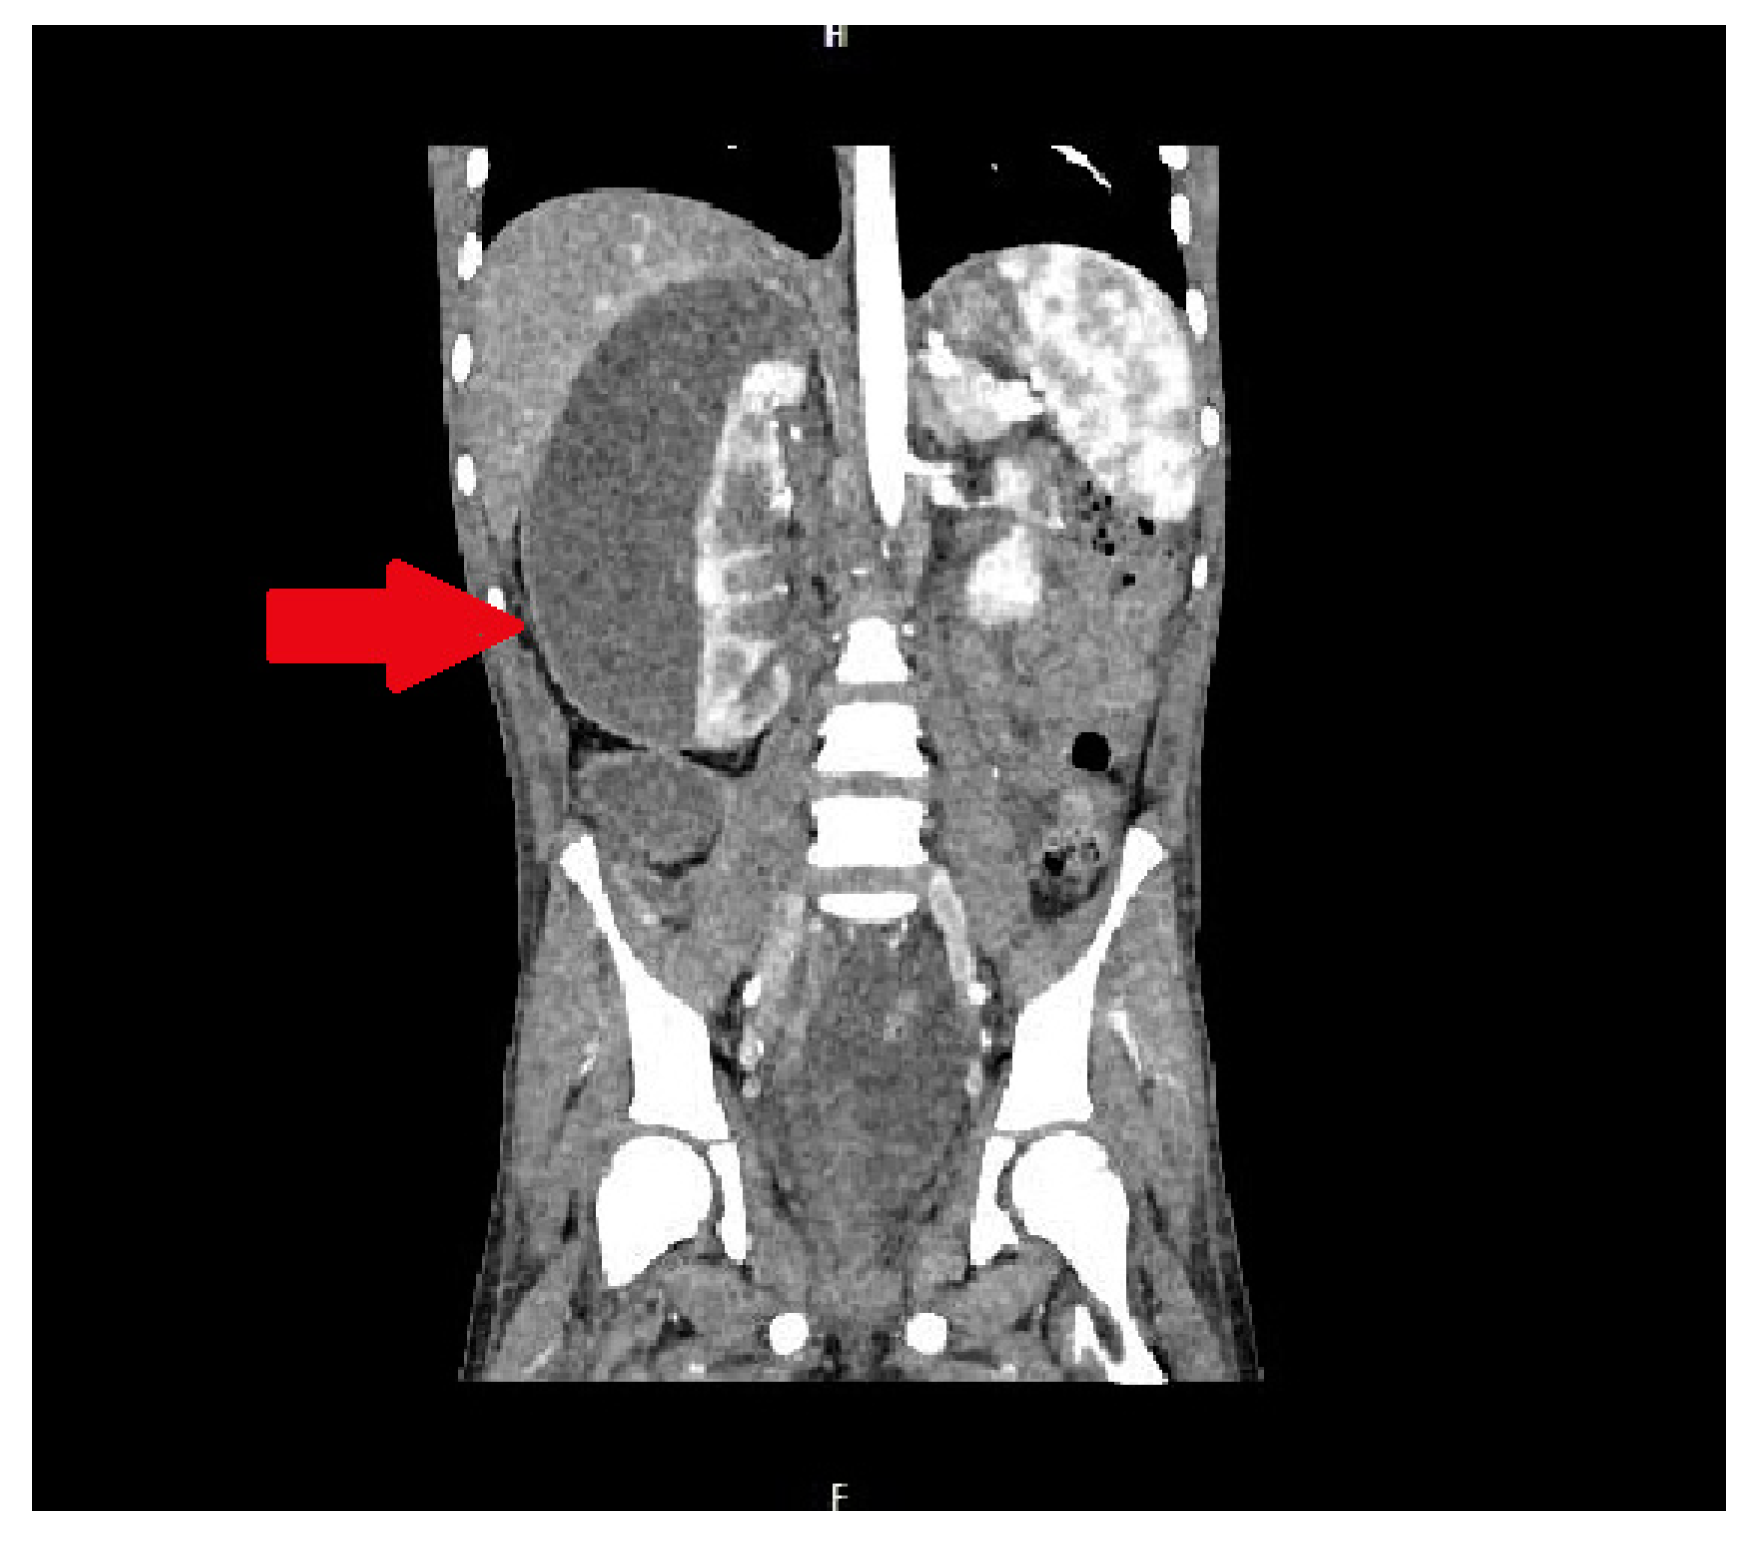

In the infectious disease ward, COVID-19 was excluded. During hospitalization, the patient developed acute abdominal symptoms. The acute condition of the boy appeared suddenly. Results of laboratory tests showed deviations in white blood cells (WBC) = 11.89 × 103/µL, and hemoglobin (HGB) = 6.9 g/dL, with hematocrit (HCT) = 20.6%. The inflammatory markers were elevated. Urinalysis showed 75 mg/dL of proteins. The ultrasound of the abdomen and computed tomography were performed. The diagnosis was unclear. Inflammation, abscess, cyst, and abdominal tumor were suggested. In the computed tomography (CT), the lesion had dimensions: 11.1 × 8.2 × 25 cm (Figure 1 and Figure 2).

It displaced and compressed the inferior vena cava and right renal vein. The lesion adhered to and modeled the liver and pancreas. It was pushing the intestinal loops. The lesion reached down into the bladder. After multidisciplinary consultation with a radiological and oncological team, the decision about surgical treatment was made. Exploratory laparotomy was performed. During the surgery, there was a large amount of purulent content in the peritoneal cavity. A large abscess was visible in the vesicorectal recess. An enormous abscess near the right kidney was localized. The abdominal cavity was thoroughly rinsed. The abdominal cavity and the perirenal space were drained. The bladder was thick and fibrous.

Figure 2. The lesion of unknown character in the area of the right kidney, shown in the frontal plane of the CT scan. The lesion is marked by an arrow.